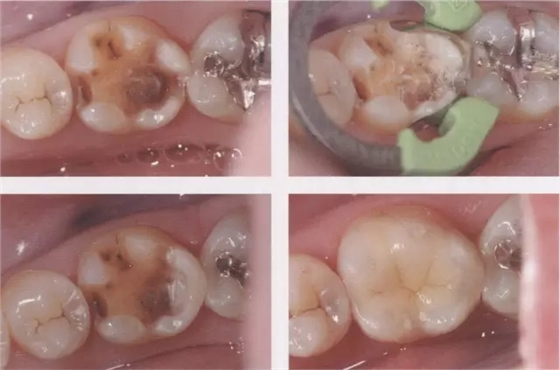

1、嵌體和高嵌體 在磨牙區(qū)域,由于牙齒近中面以及遠(yuǎn)中面的傾斜程度不同,常會遇到分離困難的病例。例如,智齒的近中根傾斜,引起鄰牙根間隙過窄的情況。相鄰牙齒的近中傾斜,牙冠進(jìn)入被處理牙倒凹處的情況(圖2、3)。以上情況,鄰接面由于齲齒形成窩洞,即便是運(yùn)氣好在齦下做了分離,也會因為出血造成取模困難、頰舌的成形變大。所以采取以下處理措施。 1、術(shù)前拍攝牙片,根據(jù)牙根的傾斜判斷有沒有引起鄰牙根間隙過窄的情況。若沒有傾斜,就是簡單病例。 2、若智齒沒有對合牙,也考慮拔除智齒。 3、鄰接面用樹脂填充之后,用間接法進(jìn)行烤瓷嵌體或烤瓷高嵌體修復(fù)。 1、貼面治療 對于變色牙齒進(jìn)行貼面治療的情況下,牙頸部觀察無變色的情況下,可直接在齦上做成形。普通成形深度能夠保存牙釉質(zhì),因而判斷為簡單病例。(圖4) 如果牙頸出現(xiàn)變色,就需要進(jìn)行齦下成形,難度增加。如果也存在前突問題,為改善變色貼面不能做厚,因而難度會更高。如果希望糾正前突、改善變色,則需要增加切削量,甚至可能進(jìn)行拔髓。另外,由于粘接對象主要是牙本質(zhì),因而需要格外注意。

圖3鄰接面成形困難的病例。如圖所示右下7近中傾斜,窩洞成形的遠(yuǎn)中側(cè)有缺損(上左),所以遠(yuǎn)中部需要在齦下做很深的成形(上右),因而選擇在遠(yuǎn)中先進(jìn)行樹脂填充后(上右)。進(jìn)行MO窩洞修整后做全瓷嵌體試戴(下)。